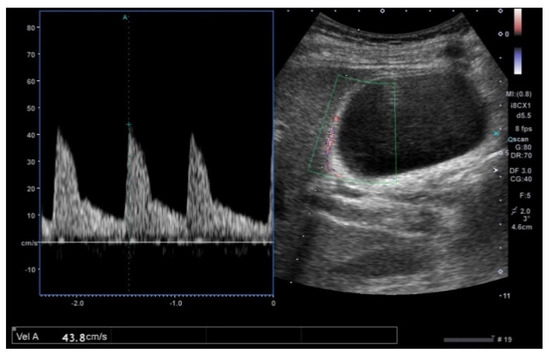

GWBF velocity in acute cholecystitis (28.6 ± 7.1 cm/s) showed a tendency to be faster than chronic cholecystitis (20.8 ± 4.6 cm/s) and ADM (16.8 ± 4.8 cm/s) [54] (Figure 15). GBC (49.4 ± 12.6 cm/s) showed significantly higher GWBF velocity (p < 0.01), and the sensitivity and specificity with the cut-off level at 30 cm/s were 100% and 96%, respectively [54]. Kawashima et al. [77] reported that the mean GWBF velocity of PBM (29.4 ± 3.9 cm/s) was significantly higher (p < 0.0001; 95% CI 5.48−13.2) than those without PBM (20.1 ± 5.9 cm/s), and the cut-off level appropriate for diagnosing PBM was estimated to be 25 cm/s. They also speculated that cell proliferation enhancing in the GB wall may contribute to a higher GWBF velocity in cases without GBC.

Figure 15. GWBF velocity. GWBF velocity showed 43.8 cm/s in acute cholecystitis.